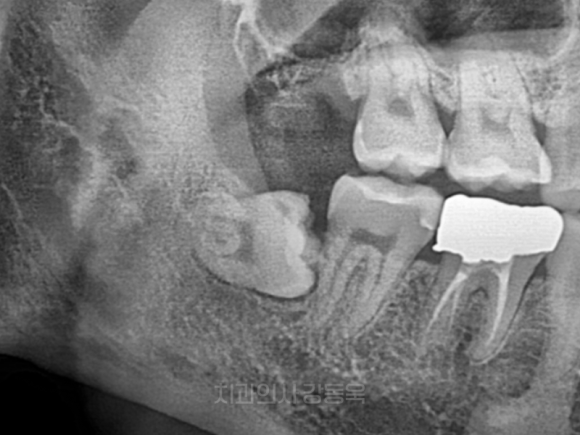

누워있는 사랑니

촬영일자: 2021.12.13

누운 사랑니 이해를 돕기 위한 참고 사진입니다.

가장 많이 보게 되는 흔한 사랑니죠.

옆으로 누워 자라면서

앞쪽 어금니를 밀고 있는 경우입니다.

이러한 경우..

앞 치아 충치를 유발하거나

잇몸에 염증이 생기거나

음식물 끼임 등의 문제가 발생할 수 있는데요.

겉으로 보기에는 문제가 없어 보일지는 모르지만

관리가 쉽지 않기 때문에,

쉽게 문제를 일으키곤 합니다.